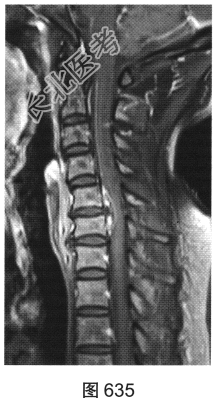

- [材料题] 患者女性,49岁,颈部胀痛伴双手麻木3天。MRI检查见图632~图637。

- 多项选择题1.患者MRI图片有哪些阳性征象( )

A、同水平硬膜囊及脊髓明显受压

B、病变与硬膜夹角为钝角

C、病变呈环形强化,中心未见明显强化

D、病变在髓外硬膜下

E、病变跨越右侧椎间孔,呈哑铃状改变

F、C

水平硬膜外梭形软组织信号

- 多项选择题2.根据MRI表现,患者可能的诊断是( )

A、脊柱淋巴瘤

B、椎间盘脱出、髓核游离

C、神经纤维瘤

D、后纵韧带骨化

E、神经鞘瘤

F、硬膜外血肿